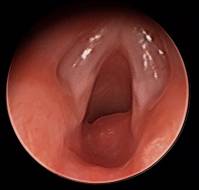

Supraglottic hemangiomas are rare vascular malformations of the larynx, particularly in children. They may cause life-threatening airway obstruction if not diagnosed..